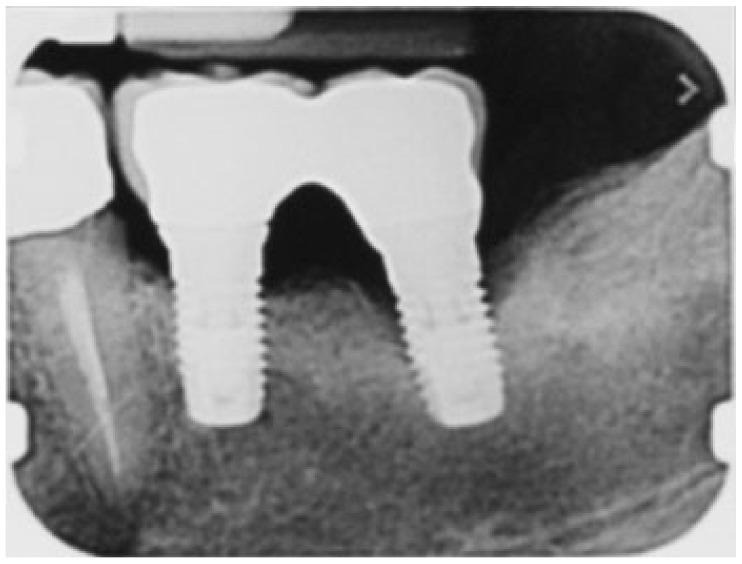

Subcutaneous facial emphysema related to dental treatments is a well-known clinical complication due to incidental or iatrogenic air or gas penetration into the subcutaneous tissues and fascial planes, leading to distension of the overlying skin. To the best of our knowledge, from 1960 to the current date, only six cases have been reported arising from peri-implant cleaning or non-surgical peri-implantitis treatment. Therefore, the present case of subcutaneous facial emphysema following open-flap air-powder abrasive debridement was the first report during surgical peri-implantitis therapy. Swelling on the left cheek and periorbital space suddenly arose in a 65-year-old woman during open-flap debridement with sodium bicarbonate air-powder abrasion (PROPHYflex™ 3 with periotip, KaVo, Biberach, Germany) of the infected implant surface. The etiology, clinical manifestations, diagnosis, potential complications, and management of subcutaneous emphysema are also briefly reviewed. The present case report draws the attention of dental practitioners, periodontists, oral surgeons, and dental hygienists to the potential iatrogenic risk of subcutaneous emphysema in using air-powder devices in implant surface debridement.

由于偶然或医源性空气或气体渗透到皮下组织和筋膜平面,导致覆盖皮肤膨胀,与牙科治疗相关的皮下面部气肿是一种众所周知的临床并发症。据我们所知,自 1960 年至今,仅有 6 例报告是由种植体周围清洁或非手术性种植体周围炎治疗引起的。因此,本病例报告为首次报告在手术性种植体周围炎治疗中,因开放式瓣空气粉末研磨清创术导致皮下面部气肿。在使用德国卡瓦公司生产的含 periotip 的 PROPHYflex™ 3 碳酸氢钠空气粉末研磨设备(德国卡瓦公司,比伯拉赫)对感染种植体表面进行开放式瓣清创术时,一位 65 岁女性的左侧脸颊和眶周突然出现肿胀。本文还简要回顾了皮下气肿的病因、临床表现、诊断、潜在并发症和治疗。本病例报告提请牙科医生、牙周病学家、口腔外科医生和口腔卫生师注意在种植体表面清创中使用空气粉末设备可能导致医源性皮下气肿的风险。